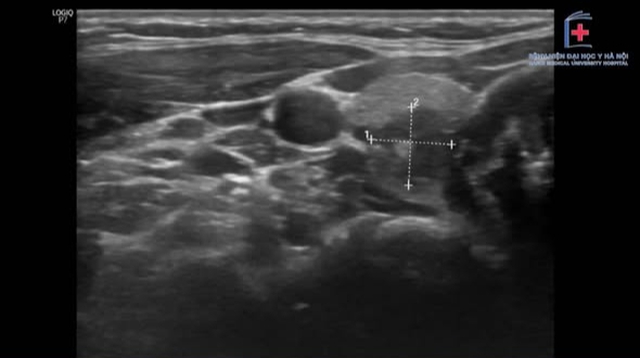

Trung tâm Ung bướu - Bệnh viện Đại học Y Hà Nội vừa tiếp nhận một trường hợp nữ bệnh nhân trẻ tuổi, phát hiện nhân tuyến giáp kích thước 8 × 8mm trong lần khám sức khỏe định kỳ.

Trước đó, người bệnh đã siêu âm tại hai cơ sở chuyên khoa, kết quả không ghi nhận hạch cổ bất thường. Điều này khiến bệnh nhân yên tâm cho rằng đây chỉ là tổn thương nhỏ, nguy cơ thấp.

Tuy nhiên, qua thăm khám trực tiếp, các bác sĩ nhận thấy khối u nằm ở vị trí có nguy cơ di căn hạch cao nên chỉ định siêu âm đánh giá lại trước phẫu thuật. Kết quả lần này chỉ ghi nhận một hạch nghi ngờ di căn, các hạch còn lại có hình ảnh lành tính.

Dù vậy, trong quá trình phẫu thuật và xét nghiệm giải phẫu bệnh sau đó, các bác sĩ phát hiện có tới 13/57 hạch chứa tế bào di căn, một số hạch đã có dấu hiệu xâm lấn ra ngoài vỏ. Điều này cho thấy mức độ bệnh lý phức tạp hơn nhiều so với những gì hình ảnh trước mổ có thể phát hiện.

Thực tế, siêu âm là phương pháp phổ biến giúp phát hiện bất thường tuyến giáp, nhưng đôi khi chưa phản ánh đầy đủ tình trạng bệnh. Một số hạch di căn có thể có hình ảnh tương tự hạch lành tính, gây khó khăn trong chẩn đoán.